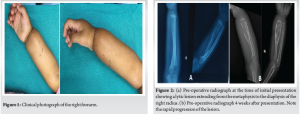

An 11-month-old girl was brought by her parents to our hospital with a complaint of pain and bony swelling in the right forearm for 5 days. There was no history of injury or fever. The pain was insidious in onset. On examination, there was bony swelling and tenderness over the distal one-third of the right forearm with no local rise of temperature. There were no scars or sinuses. The skin over the forearm was normal (Fig. 1). Passive movements in the wrist, elbow, and forearm were normal.

We evaluated the patient through comprehensive blood investigations and radiological imaging modalities. The white blood cell count was 13,000 cells/mm3. Erythrocyte sedimentation rate was 28 mm/h and C-reactive protein levels were <5 mg/L. A radiograph of the right forearm revealed an expansile lytic lesion with septations in the distal one-third of the radius extending from the metaphysis to the diaphysis with a narrow zone of transition and clear boundaries (Fig. 2). Magnetic resonance imaging (MRI) of the forearm showed an ill-defined altered signal, hyperintense on the proton density fat-saturated sequence and hypointense in T1 involving the metadiaphyseal region of the distal radius for a length of 5 cm (Fig. 3a).

The diagnosis was confirmed as LCH based on histopathological and IHC analysis. The diagnostic imaging and biopsy were done over a span of 4 weeks. The lesion’s radiographic appearance evolved rapidly over this period, raising concern (Fig. 2). After pre-anaesthetic evaluation, curettage and intralesional steroid injection was planned under general anaesthesia. The extent of the lesion was marked using C-arm fluoroscopy. A skin incision was made on the volar aspect of the right forearm. The lesion was exposed through the modified Henry’s approach (Fig. 5a). Intra-lesional curettage was done. After curettage (Fig. 5b), 1 mL of methylprednisolone acetate (40 mg/mL) was injected into the lesion. After surgery, the right upper limb was splinted (Fig. 5c) in an above-elbow Plaster of Paris back slab to prevent a pathological fracture.

LCH is a rare lesion that is characterised by the presence of Langerhans cells, histiocytes with distinctive racquet-shaped Birbeck granules that are visible under electron microscopy. LCH is a part of a wide spectrum of disorders referred to as Histiocytosis X, which comprises syndromes such as Hand–Schüller–Christian disease and Letterer–Siwe disease. Solitary LCH constitutes up to 80% of histiocytosis X lesions in children, with nearly 90% of cases occurring in pediatric populations [3]. While the exact pathogenesis remains unclear, infectious, immune, and neoplastic causes have been proposed [3]. The most frequently affected bones are the skull (34%), spine (15%), ribs (7%), and long bones (15%), with the diaphysis being the most commonly involved region in long bones (58%), followed by the metaphysis [4]. The clinical presentation is heterogeneous and non-specific, encompassing symptoms such as pain and localized swelling, as well as incidental detection during imaging conducted for unrelated conditions or trauma. In certain cases, pathological fractures may be observed. Physical examination typically reveals no significant findings, and laboratory investigations are generally non-specific, though a mild elevation in erythrocyte sedimentation rate may occasionally be noted. Radiographically, acute lesions are typically seen in the metaphysis or diaphysis characterized by aggressive, lytic, medullary-based patterns with poorly defined margins, making differentiation from infection or Ewing’s sarcoma challenging [5]. Over time, these lesions may develop more distinct features, including sclerotic scalloping, cortical erosion or thickening, widening of the medullary cavity, periosteal reactions (such as “onion peel” appearance), and potential soft tissue involvement [5]. In our patient, the lesion grew at an alarming rate in a span of just 4 weeks (Fig. 2), prompting a thorough evaluation and prompt surgical intervention. It is crucial to differentiate LCH from conditions such as osteomyelitis and Ewing’s sarcoma, as the management strategies and prognostic outcomes for these conditions differ significantly, with substantial implications for the patient’s treatment and overall prognosis. Imaging modalities such as CT and MRI are particularly useful in evaluating soft tissue extension, with MRI being highly sensitive for detecting bone marrow changes and associated soft tissue masses, although the findings are often non-specific [3]. Bone scintigraphy, however, is of limited utility, detecting only 35% of lesions [6]. Definitive diagnosis relies on biopsy, with confirmation achieved through immunohistochemical markers, such as S100, CD1, and OKT6, or electron microscopy. A solitary bone lesion rarely progresses to involve multiple bones or visceral organs. However, patients presenting with a single lesion should undergo comprehensive evaluation to exclude the presence of additional lesions. PET scans are highly sensitive for identifying LCH lesions and assessing therapeutic response, but are costly, involve significant radiation exposure, and have limited availability. It is not recommended to change the method of evaluation (radiographs), as it may lead to discrepancy in future assessments [7]. Following the ALARA principle (as low as reasonably achievable), follow-up imaging should focus on the initially affected region to minimize radiation exposure. Treatment approaches for solitary EG vary. While spontaneous remission is possible, observation or biopsy alone to confirm the diagnosis has been suggested as a treatment approach. A study of six skeletally immature patients reported spontaneous resolution without recurrence after biopsy (three open and three percutaneous), indicating that surgery might have a higher recurrence risk than less invasive methods [8]. Conservative treatment for EG can be unpredictable and may lead to significant morbidity, including pain, restricted activity, growth disturbances, or pathological fractures [9]. Chemotherapy is generally not recommended for solitary lesions and should be reserved for systemic disease or solitary lesions in high-risk, non-resectable locations [9,10]. Radiotherapy is rarely utilized due to the risk of inducing latent neoplasms [11]. Systemic therapies, such as chemotherapy and corticosteroids, are generally reserved for cases of multisystem disease and are avoided in solitary lesions due to their toxicity and unpredictable efficacy [12]. Symptomatic and surgically accessible lesions are typically treated with biopsy, curettage, and bone grafting, if necessary [13]. Local corticosteroid injections have demonstrated favorable outcomes, including pain resolution and lesion healing within 2 months [14]. The mechanism of intralesional corticosteroids remains unclear. A study of 39 patients with solitary EG found that percutaneous needle biopsy and intralesional methylprednisolone effectively relieved pain, avoided surgery, and achieved osseous healing in 97% of cases [15]. Chadha et al. reported a similar lesion in the radius of an 11-year-old patient, which was treated with curettage. At 2 years of follow-up, there was complete resolution of the lesion with remodelling of the cortex [16]. A bony lesion that usually presents with pain, without soft-tissue involvement, is the most common presentation and has the best prognosis. Other favorable prognostic factors include age >2 years and the lack of pulmonary, hepatic, hematopoietic lesions, or multiple bone involvement [4].